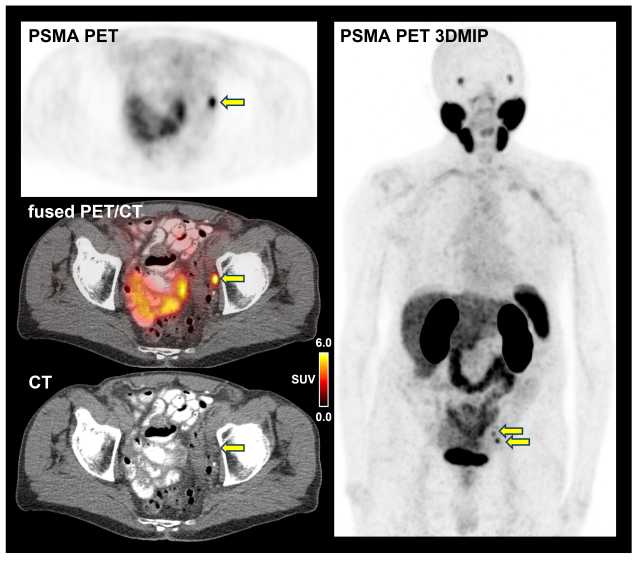

This advanced imaging technology plays a critical role in redefining how prostate cancer is staged. PSMA-PET imaging uses tiny amounts of radioactive “tracers,” called radiotracers, that binds to prostate cancer cells, making them visible on PET scans. Unlike conventional imaging, which provides only anatomical details, PSMA-PET offers functional imaging that reveals the cancer’s biological activity, which can significantly improve the accuracy of disease staging.

In the cohort of patients, the researchers found PSMA-PET detected cancer metastases in 46% of patients, even though traditional imaging had suggested no evidence of cancer spread. Based on PSMA-PET, 24% of the patients even showed 5 or more lesions that had been missed by conventional imaging.